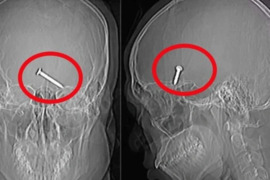

Dəhşətli iş qəzası! Gözündən girdi, beynindən çıxdı!

Malayziyada tikitinti aparılan ərazidə baş verən iş qəzası qorxulu anlar yaşadıb. xarici mənbəyə istinadən xəbər verir ki, tikintidə qoruyucu eynək taxmadan işləyən 30 yaşlı inşaat işçisi üzünü mismar vuran maşına yaxınlaşdıran zaman gözünə mismar girib. Mismar maşınının qəfil işləməsi nəticəsində so